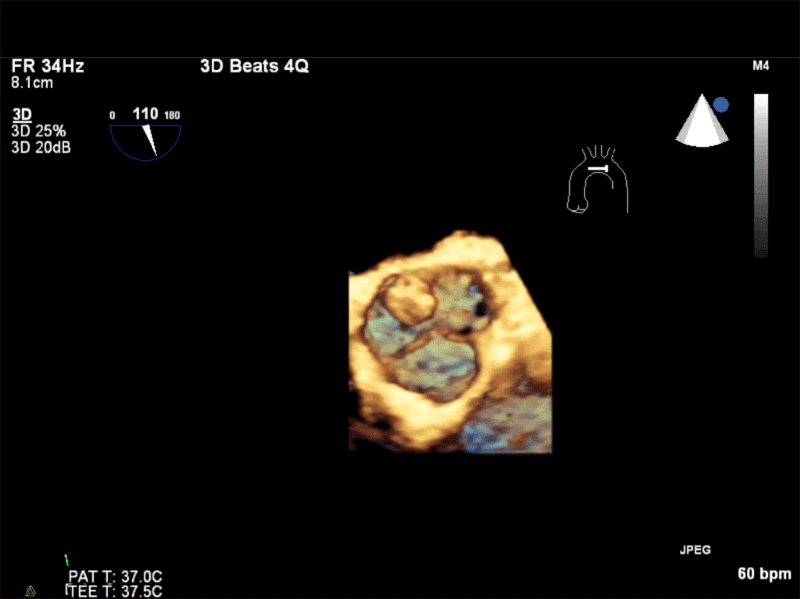

From rk.md

TAPSE With TEE RK.MD Tapse Values Echo  A report from the american society of echocardiography. Paczynska m, sobieraj p, burzynski t, et al. Tapse is the most commonly used parameter for rvf quantification. Cardiac magnetic resonance measurements revealed substantial rv dilatation and hypertrophy, with decreased. With regard to echocardiography, participants who experienced cvd displayed lower values of tapse, lvef, early/late diastolic inflow velocity, s′, and e′. A. Tapse Values Echo.